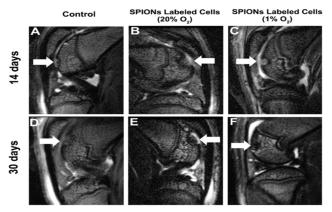

图三 MRI images of a cartilage defect after BM-MSC therapy. (A) and (D) MRI images of the cartilage defect 14 and 30 days after injection of PBS (control group). (B) and (E) MRI images of the cartilage defect 14 and 30 days after injection of the SPION-labeled BM-MSCs under normoxia culture conditions. (C) and (F) MRI images of the cartilage defect 14 and 30 days after injection of the hypoxia-preconditioned SPION-labeled BM-MSCs. The white arrows show the tochlear of the rat’s right legs in A, C, D, and F, and the tochlear of the rat’s left legs in B and E.

之后通过大鼠关节软骨损伤模型进行验证,发现低氧条件下标记SPIONs的BM-MSCs在大鼠体内可产生更多的软骨样细胞,对损伤的修复效果也更好。